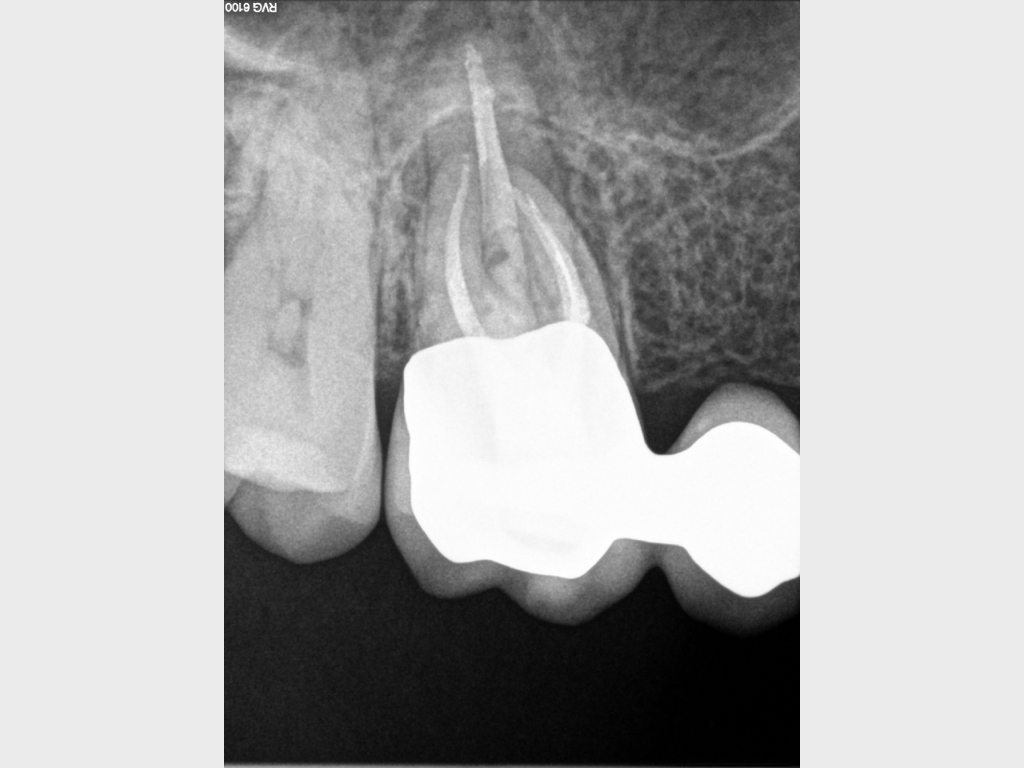

Heilung Express oder Radiodontics